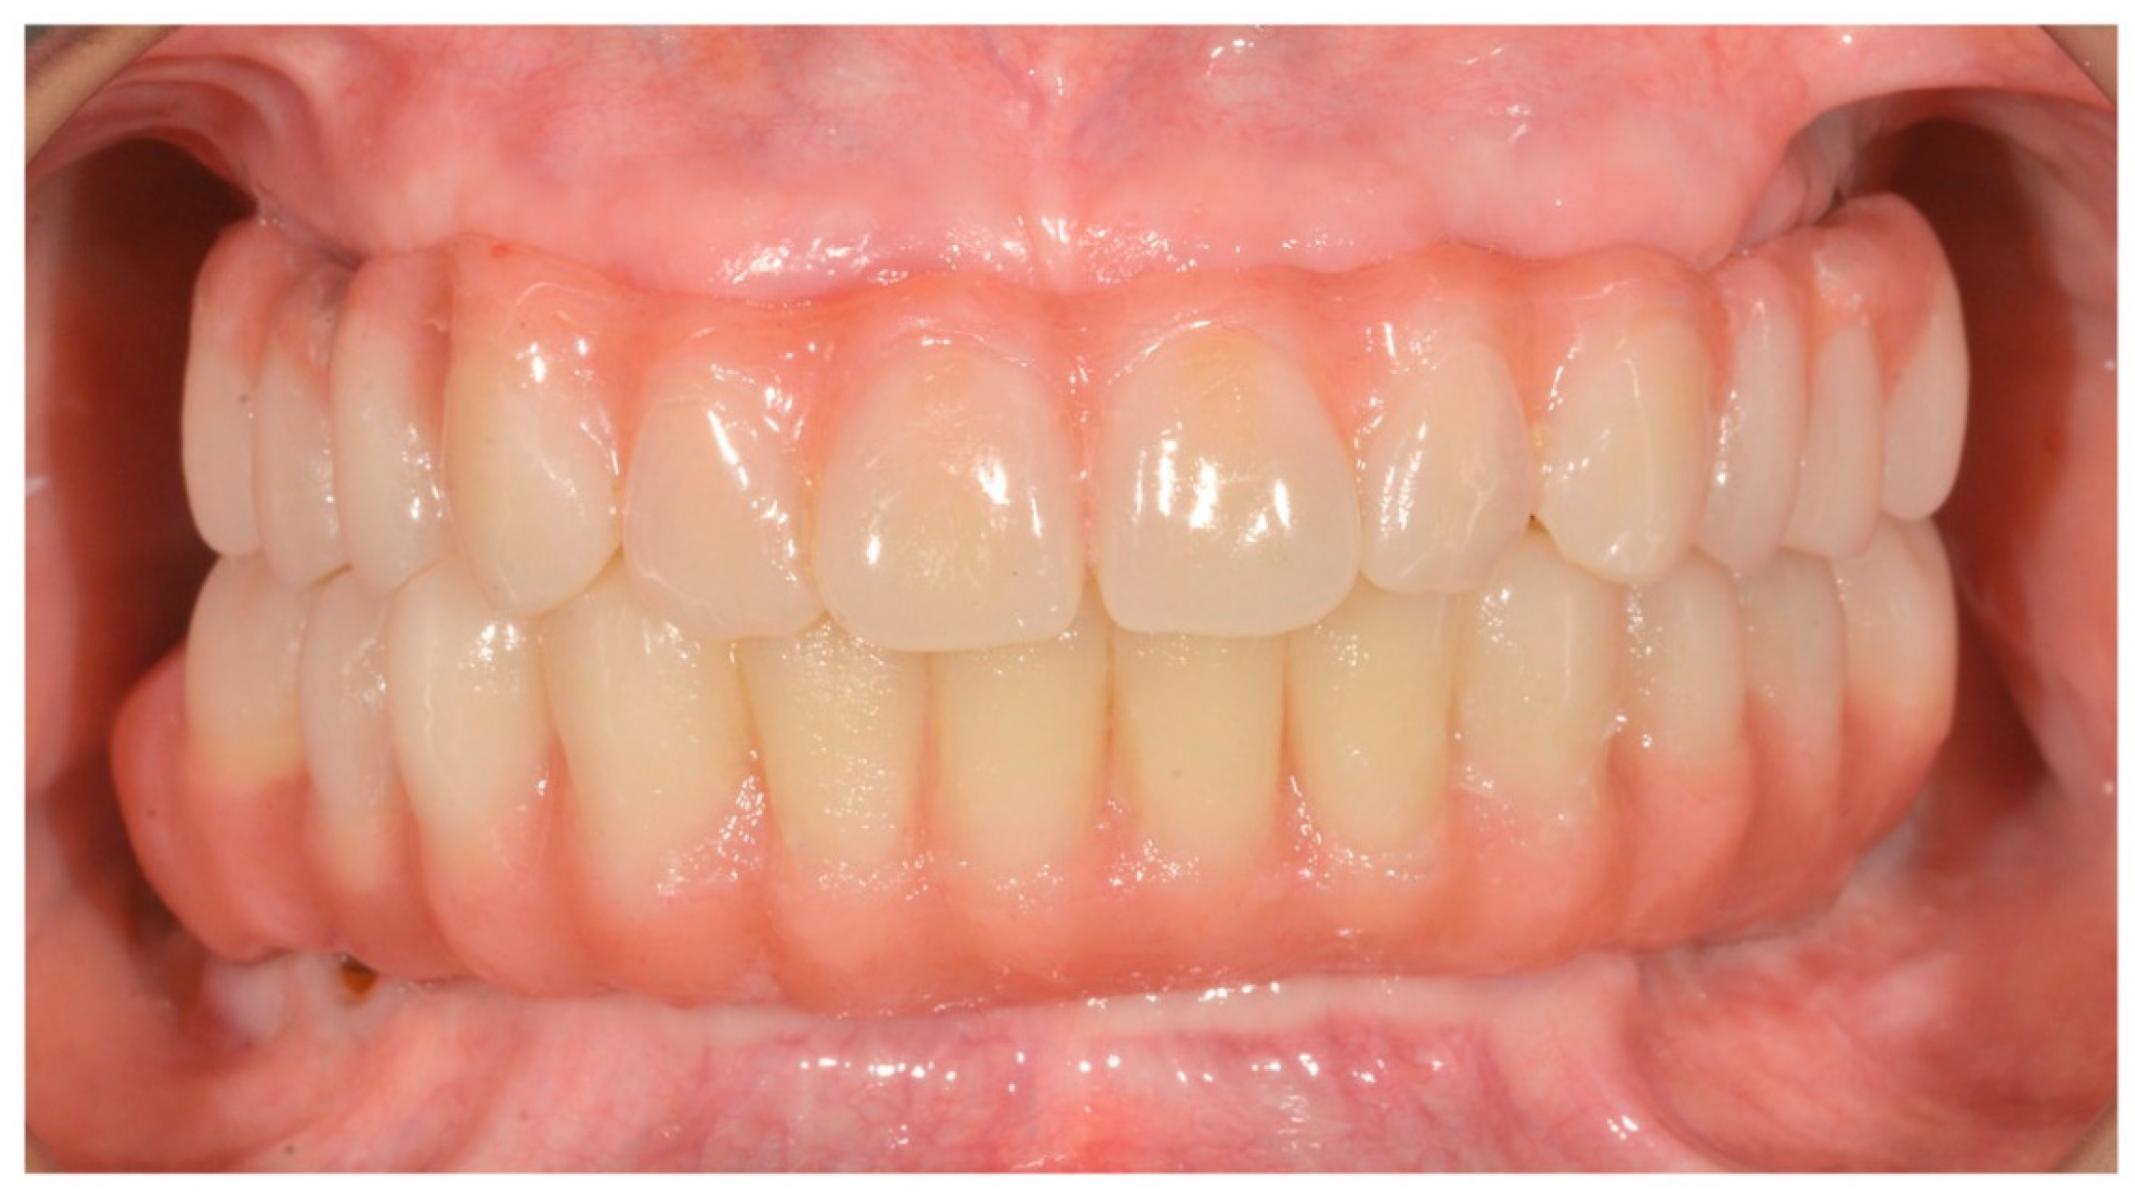

4. Results